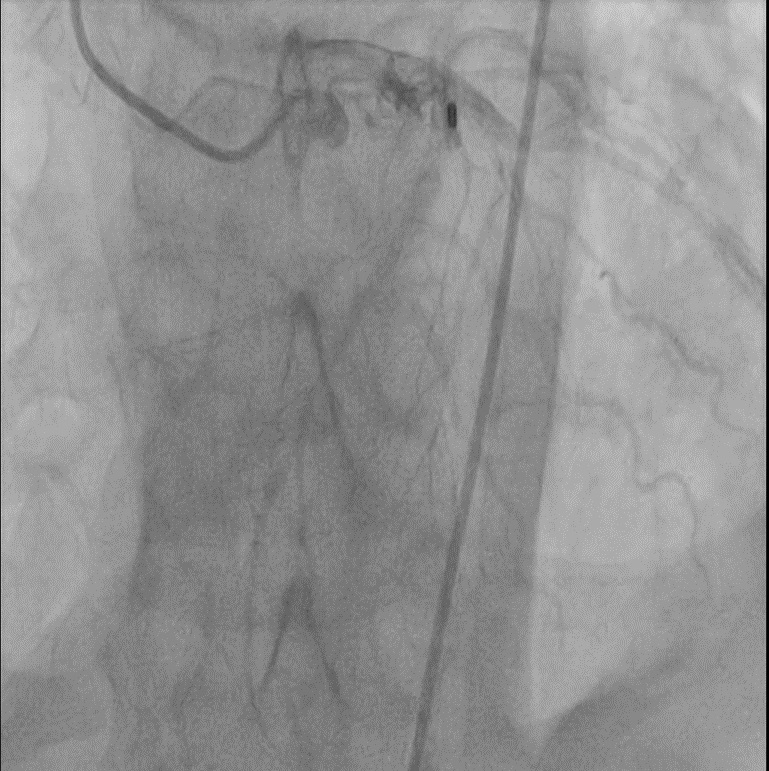

A 65-year-old hypertensive, diabetic male presented with acute anterior wall MI (window 72 hrs) complicated by cardiogenic shock and apical ventricular septal defect (VSD) on echocardiography, showing a significant left-to-right shunt with severe PAH and EF 35%. An intra-aortic balloon pump (IABP) was inserted for hemodynamic stabilization. The procedure was performed via dual access — 6F femoral arterial sheath and 8F internal jugular venous sheath. The left ventricle was cannulated, and the VSD was carefully crossed using a catheter and guidewire, which was advanced into the pulmonary artery. The wire was then snared through the VSD defect to establish an arteriovenous loop, providing stability for device delivery. Over this loop, an Amplatzer 14 mm ASD device was advanced through the 8F sheath and positioned across the apical VSD under echocardiographic and fluoroscopic guidance. After confirming proper alignment and stability, the device was successfully released, achieving complete closure of the shunt. Immediate echocardiography confirmed no residual flow across the septum. The patient was transferred to the CCU for monitoring, with gradual IABP weaning over 4–5 days. Follow-up echocardiography before discharge showed no residual shunt, improved hemodynamics, and stable LV function.